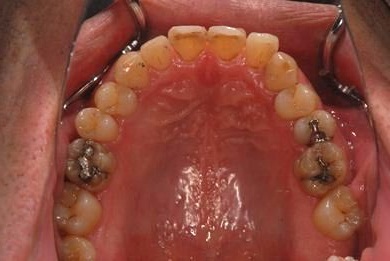

| 性別/年齢 | 男性 / 37歳 | ||||||||||||||||||||||||||||||||

| 主訴 | 前歯(2本)の欠けの治療 | ||||||||||||||||||||||||||||||||

| 治療方針 | 右下欠損部分をインプラント治療にて、機能的・審美的回復を行う。 | ||||||||||||||||||||||||||||||||

| 治療内容 | インプラント1本、メタルボンドセラミッククラウン1本 | ||||||||||||||||||||||||||||||||